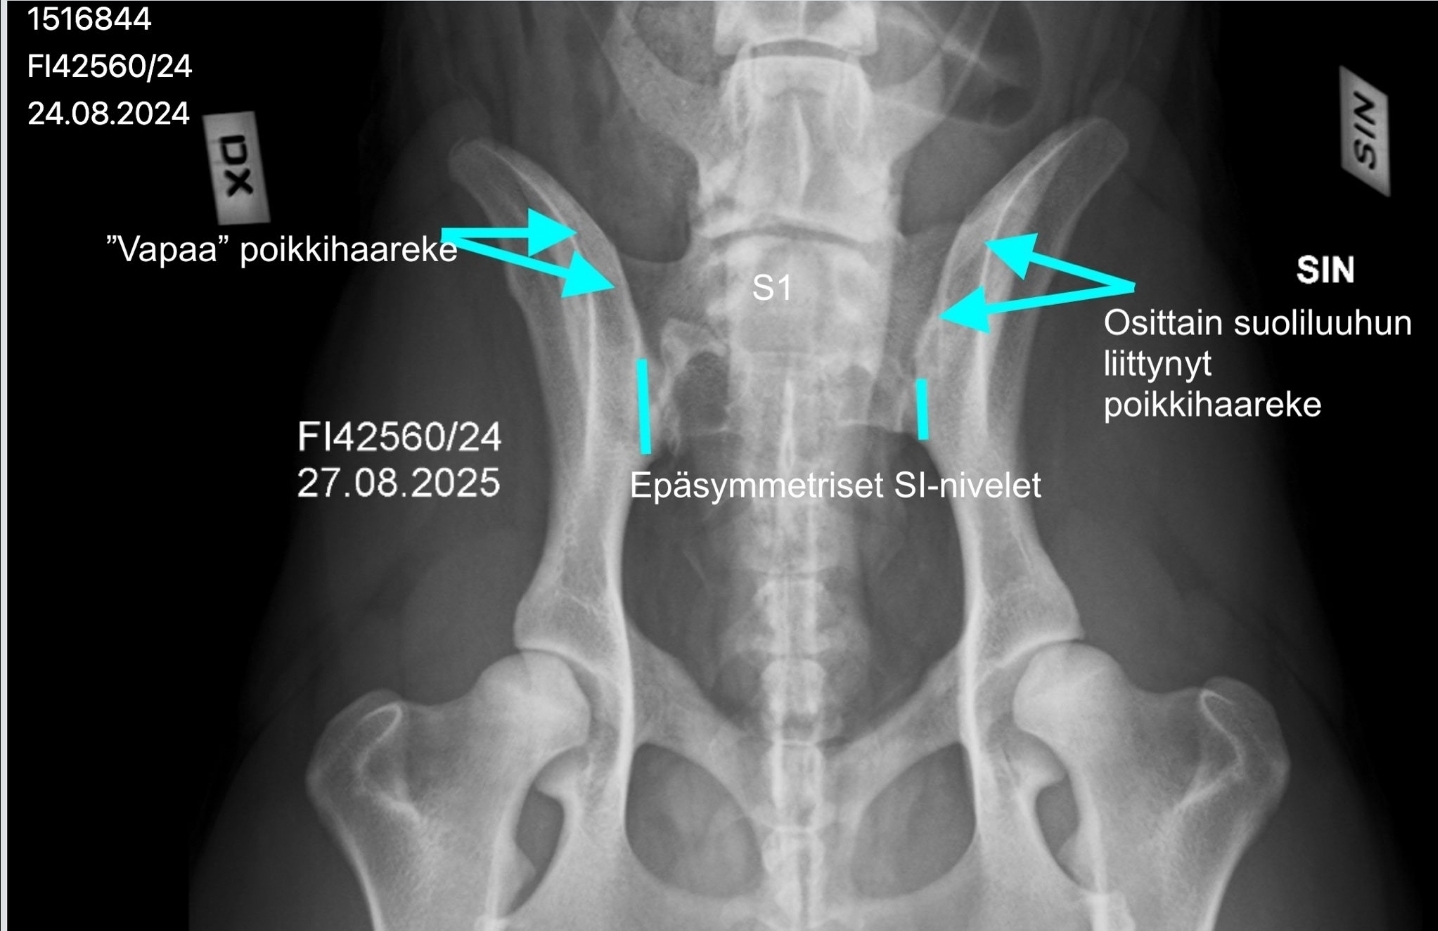

Koiran ensimmäinen ristinikama S1 on epäsymmetrinen ristinikaman ja lannenikaman välimuoto. Se on irti toisesta ristinikamasta ja siinä on epäsymmetrinen poikkihaarakkeet, joista toinen on "vapaa" ja toinen on osittain yhdistynyt suoliluuhun. Lisäksi koiran risti-suoliluunivelet (Sl-nivelet) ovat epäsymmetriset.